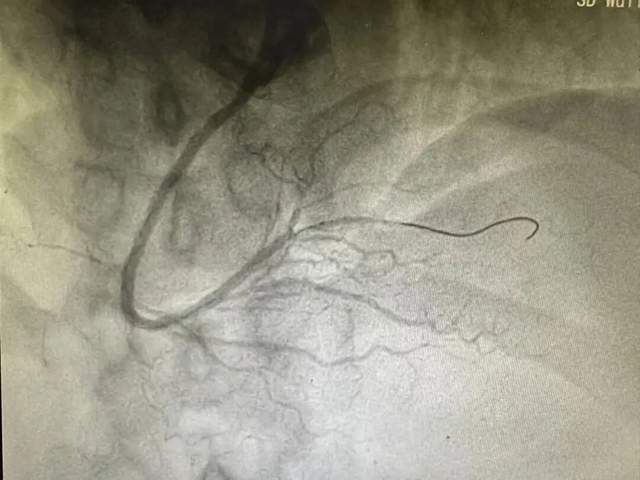

● 生命体征平稳后,通过导丝、球囊扩张闭塞血管后,在右冠状动脉近中段植入一枚支架,术后造影显示支架贴壁良好,TIMI血流三级。

植入支架后造影图像

这场救治的关键,在于及时的电除颤稳住生命,以及支架植入打通堵塞血管,恢复心肌供血。